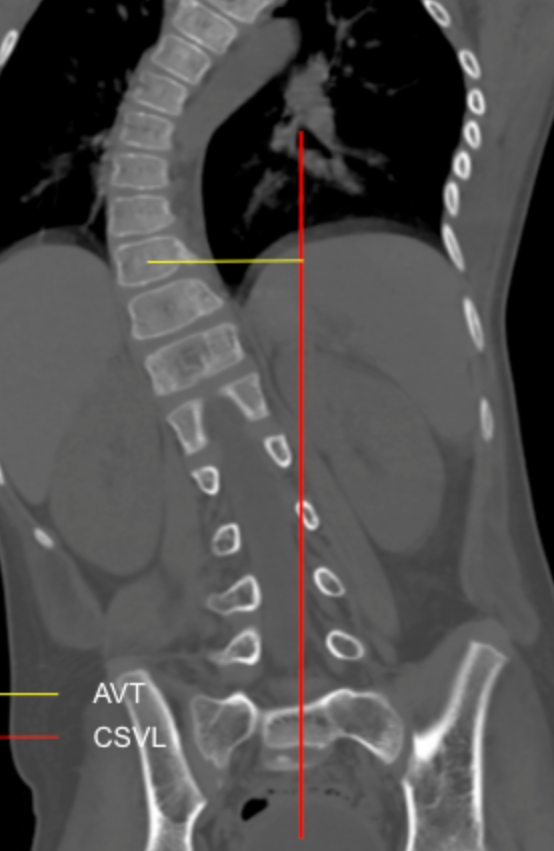

Apical Vertebral Translation (AVT)